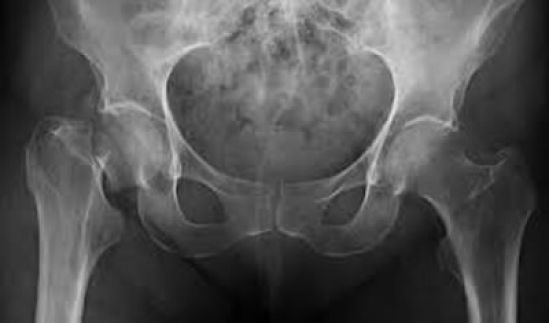

La osteoporosis es una enfermedad esquelética sistémica que se caracteriza por la pérdida de masa ósea y un cambio en la estructura de esta, lo que conlleva tener huesos más frágiles y susceptibles a fracturas. Las personas que padecen este padecimiento presentan dolor, deformidad e incapacidad funcional, principalmente de las articulaciones con gran movilidad o que soportan peso.

“Una de las consecuencias más graves de esta enfermedad son las fracturas, ya que implica un alto riesgo de pérdida de independencia, dolor crónico y necesidad de rehabilitación”, señaló el Dr. Rolando Espinosa, Presidente de la AMMOM; quien destacó que “es necesario contar con un programa integral que abarque todas las aristas del padecimiento, desde la prevención hasta la educación médica continua, poniendo atención en el diagnóstico oportuno una vez ocurrida una primera fractura, para así evitar eventos subsecuentes”.

En personas mayores de 50 años cualquier fractura debe considerarse como un evento significativo para el diagnóstico de osteoporosis; las fracturas pueden evolucionar hacia una recuperación total o con dolor crónico, discapacidad y muerte. Por ejemplo, las fracturas de cadera en el primer año se asocian con una

elevada mortalidad, que oscila de 8 a 36%, además, confieren 2.5 veces más riesgo de nuevas fracturas.

actualmente en México la población de más de 60 años rebasa los 12 millones de personas”, destacó además que, “las fracturas más comunes se producen en la columna, muñeca y cadera; en particular, las de columna y cadera pueden provocar dolor crónico, incapacidad, e incluso la muerte”.

En México, en el 2005, el número total de casos de fractura de cadera fue de 21,000 aproximadamente, se proyecta que para 2050 llegue a 110,055, lo que significa un aumento del 431%. Para este año también se estima que el 37% de los mexicanos mayores de 50 años padezca osteoporosis.